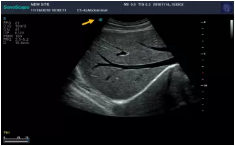

Mark點(diǎn):每一把探頭都有一個(gè)mark點(diǎn),是用于定位方向, mark點(diǎn)一側(cè)始終對(duì)應(yīng)著圖像S點(diǎn)(圖像箭頭標(biāo)識(shí))一側(cè)。